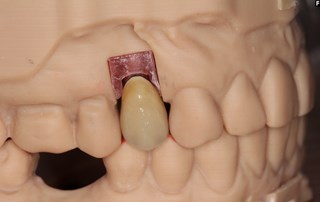

Kronan klar för montering i munnen